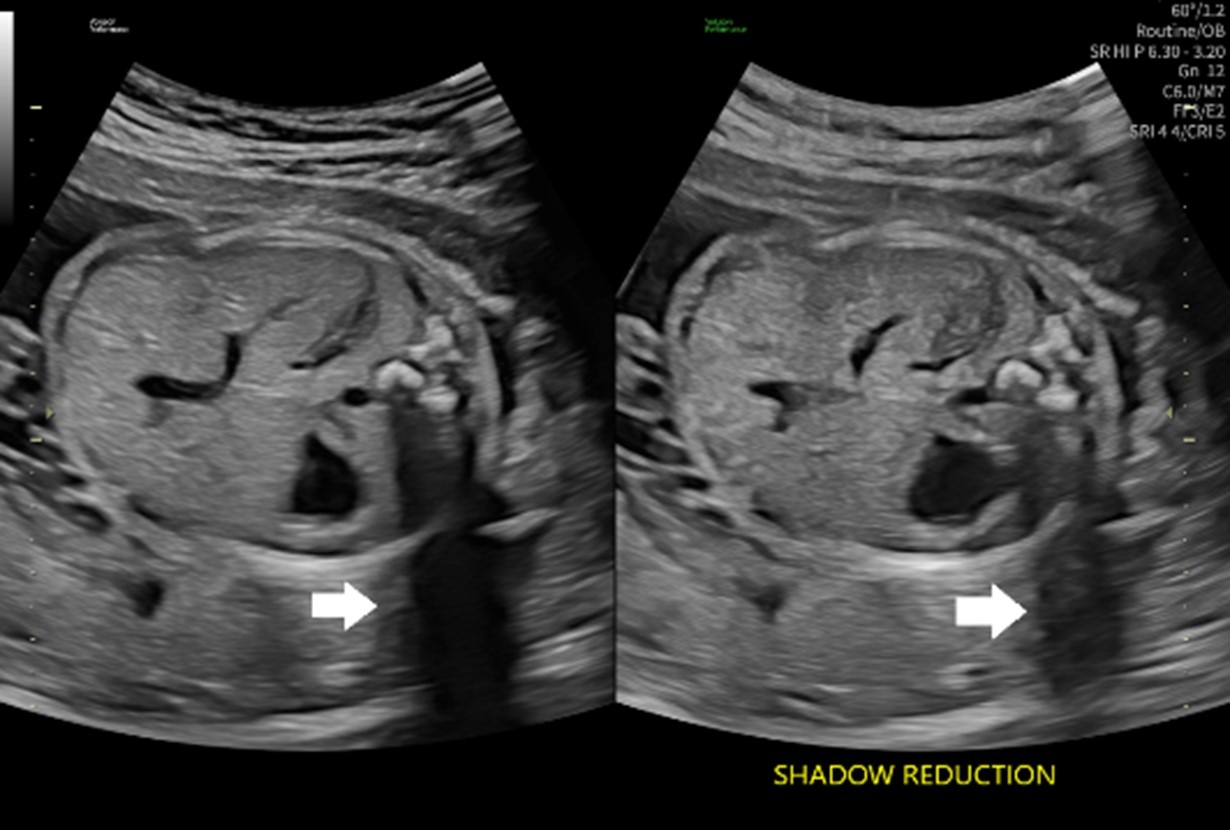

【画像】音響陰影を補うShadow Reductionの比較(左 off/右 on)